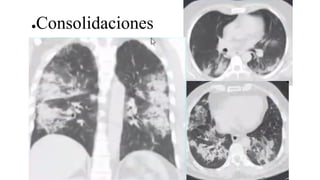

●Consolidaciones

Patrones tomográficos sugestivosde infección por COVID-19

●Opacidades periféricas envidrio esmerilado (con o sin consolidación)